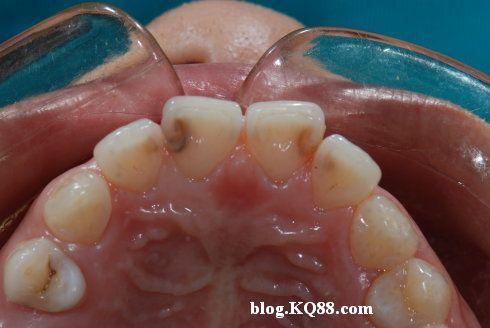

不要以为你的宝宝没有喝咖啡牙齿就不会变色,有些疾病,或是珐琅质质量不佳、牙齿受伤、刷牙不正确等,都可能导致小婴儿的牙齿变色。因此,你应该每天帮孩子刷牙,并让他补充足够的钙和维生素D等营养。下面的小编为大家分享宝宝牙齿变色的原因,只有清楚了宝宝牙齿变色的原因才能更好的科学的护理宝宝的牙齿,宝宝的牙齿如何清洁呢?宝宝牙齿变色有危害吗?宝宝是因为疾病牙齿变色吗?大家一起来看吧。

疾病或是宝宝长牙时高烧、营养不正确、长牙时的任何感染、唐氏症、先天性梅毒、黄疸等都可能导致婴儿的牙齿变色。

宝宝的珐琅质有可能因为某些原因而质量不良,像是遗传、过度吸吮柑橘水果、牙菌斑广泛累积、缺乏维生素D等,这些都可能导致宝宝的牙齿珐琅质质量不佳而变色。

宝宝的牙齿或牙龈受伤可能会导致牙齿损伤,这会导致宝宝牙齿变色。它可能有紫色、粉红色或灰色的色调。